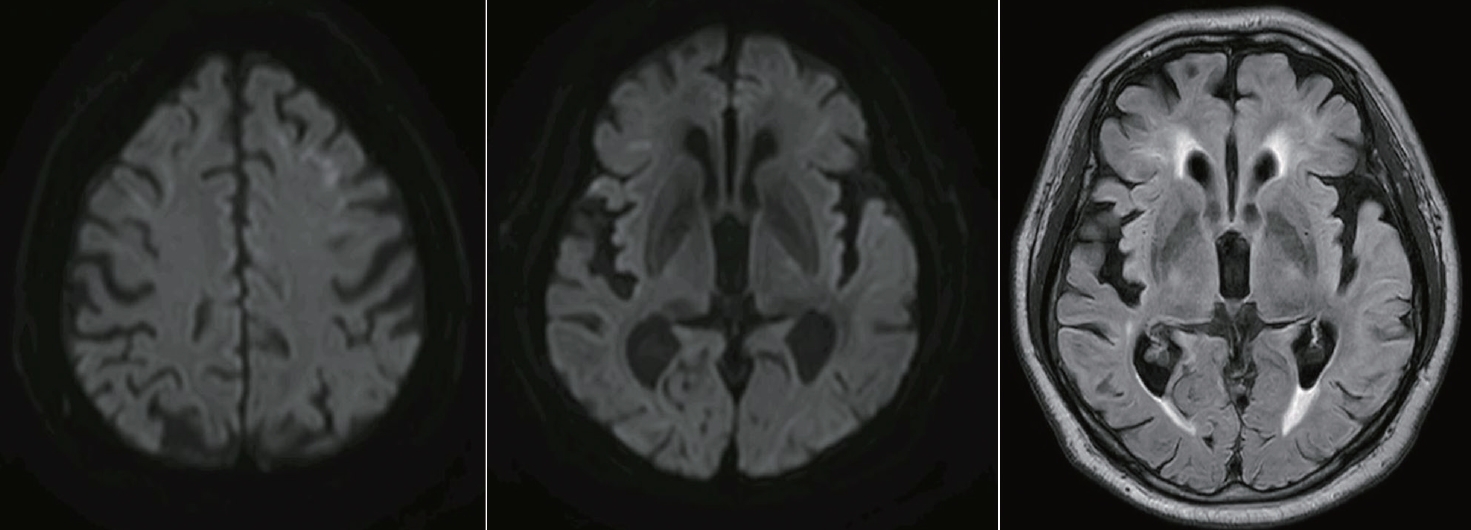

이에 발작 후 혼동을 우선 의심하여 항경련제를 우선 시작하였으며(lacosamide 100 mg 하루 2회), 3일간 입원 중 임상 경과를 관찰하였으나 완전실어증은 호전 없이 “몰라” 등의 발화만 가능한 상태가 지속되었다. 3일 뒤 추적한 뇌MRI에서는 DWI에서 양측 전두엽의 피질수질접합부와 좌측 측두엽의 고신호강도와 함께(Fig. 2-A) T2 액체감쇠역전회복(fluid-attenuated inversion recovery, FLAIR) 좌측 측두엽에 전반적인 부종 및 고신호강도가 관찰되었다(Fig. 2-B). 관류(perfusion) 영상에서는 좌측 측두엽의 전반적인 관류 저하가 확인되었다(Fig. 2-C).

Figure 2.

Follow-up brain MRI of the patient. Three days after hospital admission, follow-up brain MRI was performed. (A) On DWI, high intensity lesion in bilateral frontal corticomedullary lesion remained, and high intensity lesion in left temporal area was newly appeared. (B) On T2 FLAIR, a high intensity lesion with edema appeared newly in the left temporal area. (C) Perfusion MRI showed hypoperfusion in the left temporal area, which was correlated with persisting aphasia. MRI; magnetic resonance imaging, DWI; diffusion weighted image, FLAIR; fluid-attenuated inversion recovery.